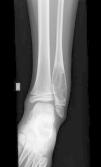

Dado el tiempo de evolución del cuadro y el dolor selectivo en maleolo peroneal se decidió solicitar radiografía simple, que evidenció lesión quística en porción diafisometafisaria del peroné distal, multiloculada, con llamativa insuflación, sin reacción perióstica (fig. 1).